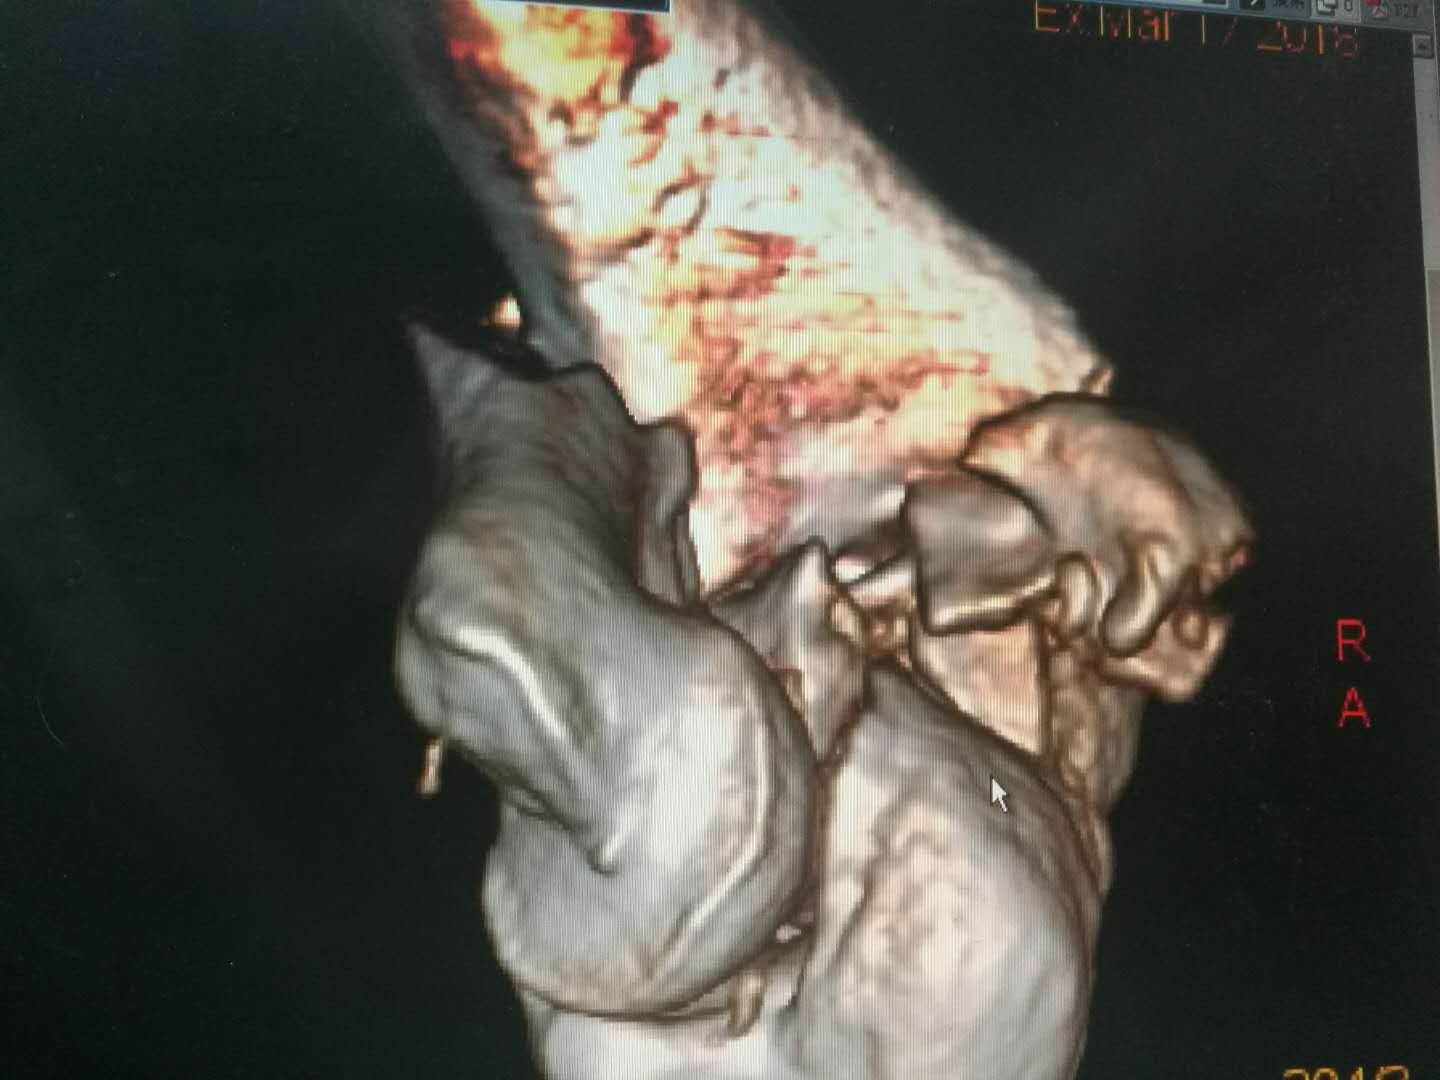

李某因不慎自约4米高处坠落,右肘部着地摔伤入院。 骨一科高长明副主任医师接诊病人后,为病人进行了仔细的查体,见其右肘部肿胀畸形,肘后有一伤口,骨头自伤口戳出,鲜血不断流淌,按压可触及明显的骨擦感,拍片见右肱骨髁粉碎性骨折,诊断为右肱骨髁开放性粉碎性骨折。开放性骨折需及早手术,但骨折粉碎,手术难度大,高医师当机立断,即刻实施手术。

术中见患者的肱骨髁已碎成20余块大小不等的骨块,均分离移位,高医师凭借丰富的手术经验,耐心地将碎骨块一块一块的拼接固定,历时3个小时,终于将骨块完好拼接,恢复了其原本的样貌。